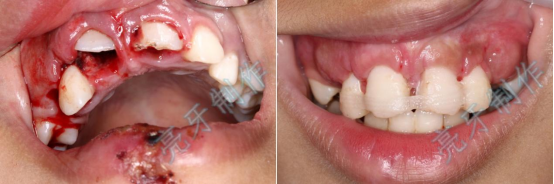

病例二:外伤导致上牙槽骨骨折,而且上下两颗门牙脱位;通过治疗,上下两颗门牙均恢复原来位置,而且和之前一样结实。